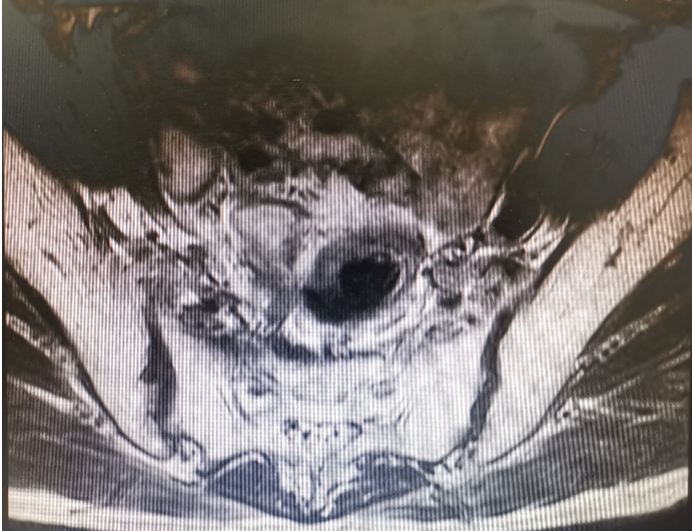

入院行MR检查提示:距离肛门10cm处粘膜面强化,周围脂肪间隙清晰,余未见异常。如图2所示。

图2 盆腔磁共振

j图2 盆腔磁共振